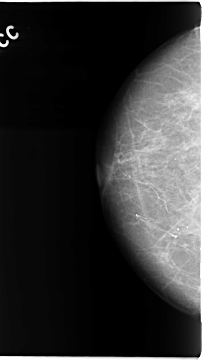

C_0067_1.RIGHT_CC

RIGHT_CC LINES 4680 PIXELS_PER_LINE 2616 BITS_PER_PIXEL 12 RESOLUTION 50 NON_OVERLAY